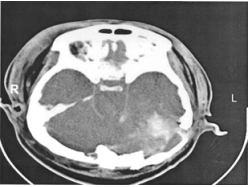

28 之後立即作了頭腦電腦斷層掃描如附圖, 顯示有顱基底骨骨折,依病史及電腦斷層 掃描,貫穿的子彈進入區是在何處?

(A)右鼻骨區 (B)左鼻骨區 (C)左後枕骨區 (D)右後枕骨區

29 警察先生的另一張電腦斷層掃描如附圖, 除了骨折,還有:

(A)左小腦內出血 (B)右小腦內出血 (C)左後腦窩硬腦膜上腔出血 (D)右後腦窩硬腦膜下腔出血